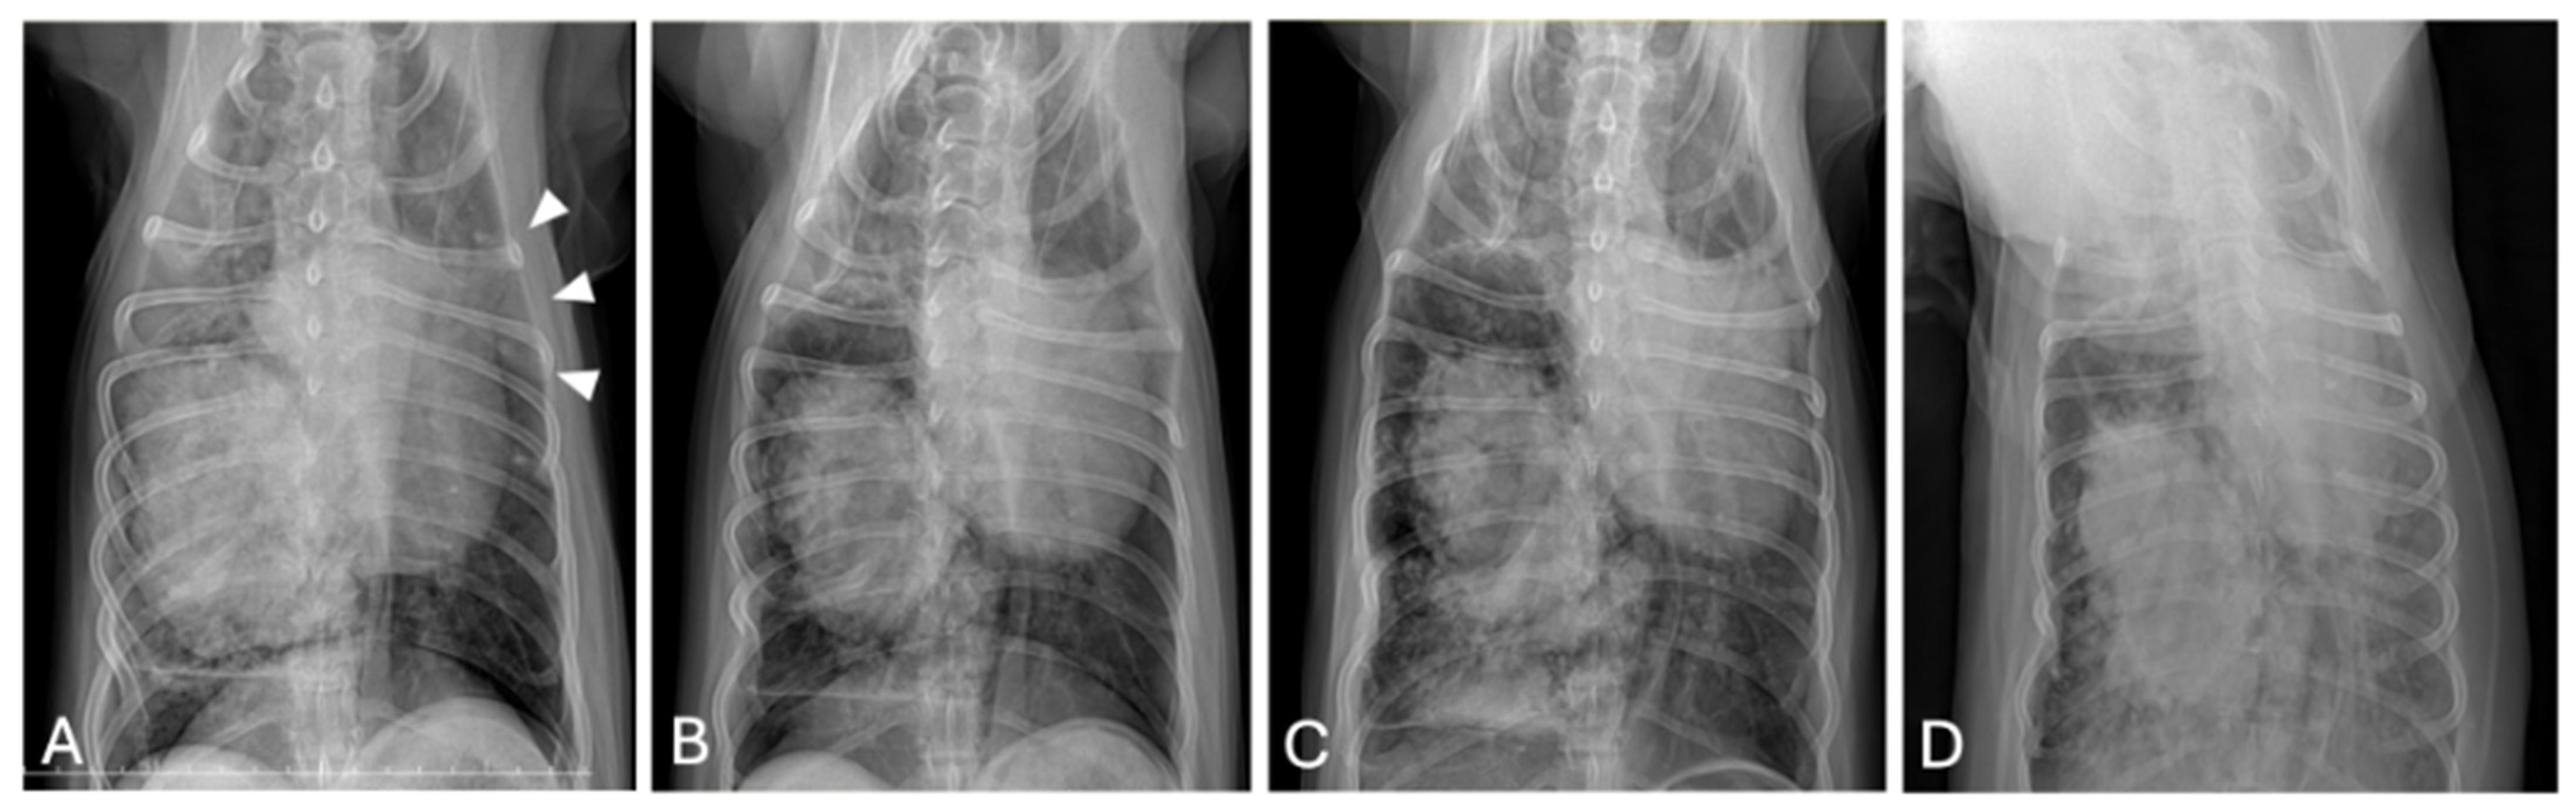

Routine follow-up thoracic radiographs at week 14 revealed a new metastatic lesion in the contralateral lung (Figure 5A), prompting reclassification to stage IV disease and resumption of combination therapy. NK cell immunotherapy was co-administered with each chemotherapy session. Vinorelbine (Navelbine®, Pierre Fabre, Boulogne, France) was re-administered at 7.5 mg/m2 IV every 10 days for four cycles, followed by 15 mg/m2 every 14 days for an additional three cycles. Stable disease was maintained for approximately 6 weeks (from week 24 to week 30; Figure 5B), although grade 1 anorexia developed after the dose was increased.

By week 30, imaging confirmed disease progression (Figure 5C), and vinorelbine was replaced with carboplatin (200 mg/m2 IV every three weeks; Carbotinol®, Korea United Pharm Inc., Seoul, Republic of Korea) while piroxicam and cytokine therapy were administered.

At 34 weeks, the dog developed acute respiratory failure. Imaging revealed extensive tumor-associated emphysema and compression of the contralateral lung (Figure 5D). The patient’s condition rapidly deteriorated, and death occurred later that day.

Figure 5. Ventrodorsal thoracic radiographs at selected key follow-up time points. (A) Week 14: A new metastatic lesion is present in the contralateral lung (arrowheads). (B) Week 24–30: No measurable change in the primary pulmonary mass compared with previous imaging. (C) Week 30: An increase in the size of the primary pulmonary mass is observed compared with prior examinations. (D) Week 34: A hyperlucent area within the mass and mediastinal shift with compression of the contralateral lung are evident.